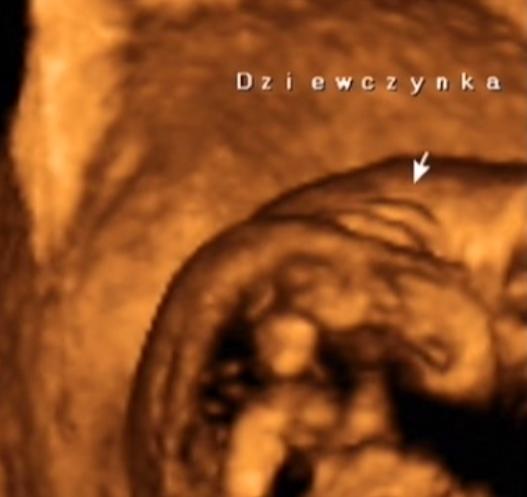

wydaje mi sie ze mozesz miec pewnosc ze nic jej nie ''przyrosnie' w kwietniu;-)